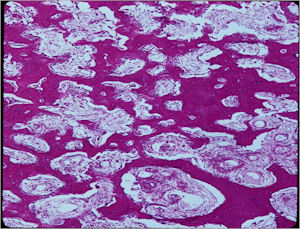

Microscopic Pathology

- Interlacing network of bone trabeculae in a loose fibrovascular stroma

- Prominent vessels

- Osteoblasts are plump, active, scattered mitotic figures

- Osteoblasts line up around periphery of trabeculae (Osteoblastic Rimming)

- Soft tissue component usually surrounded by shell of reactive bone or periosteum (Egg Shell Rim of Calcification)

- No cartilage production (as opposed to osteosarcomas that may contain areas of cartilage)